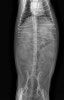

방사선 검사

수술전 방사선검사 / 출처: 라온동물메디컬센터

방사선 검사에서는 비정상적으로 확장된 자궁 음영이 관찰되었습니다.